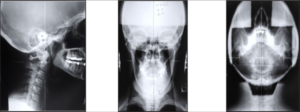

An accurate diagnosis of cervical spondylosis can only be reached by acquiring imaging of the cervical spine. Several forms of imaging may be used to identify areas of spinal degeneration, including:

The most common and in-house imaging is X-ray, however, should we not see symptoms improve at least 50% within the first 4-6 weeks, we will recommend further imaging, especially MRI. These tests will reveal the segments of the spine that are involved, the severity of spinal degeneration, and the underlying alignment issues. As a corrective, upper cervical specific chiropractic care facility, we take very precise views that will determine not only the areas of misalignment and instability, but EXACTLY how to adjust you using specific vectors to personalize your care.

Not all chiropractic approaches are created equally. Patients with spinal degeneration should seek out upper cervical chiropractors because of the unique nature of their evaluation and management. These doctors can perform precise, effective and gentle adjustments without irritating areas of spinal degeneration, risking injury, or twisting, popping, or cracking the spine.

Pic

DOES THIS LOOK LIKE YOU???